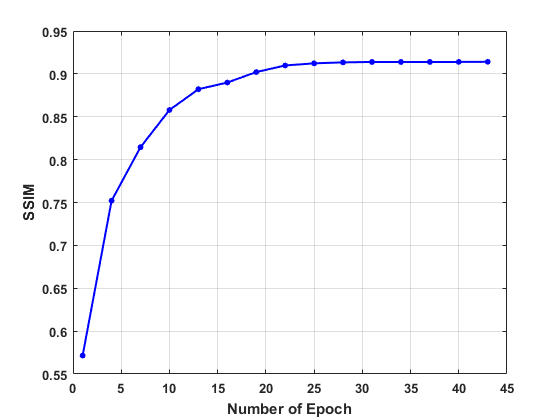

In the first place, we test the effect of the number of epoch on the convergence in network training on the human dataset. The values of the loss function, PSNR, and SSIM are plotted in Fig. 3, which evidence the convergence of our LRIP-net. Accordingly to plots, we fix the number of the epochs as during the training in the following experiments.